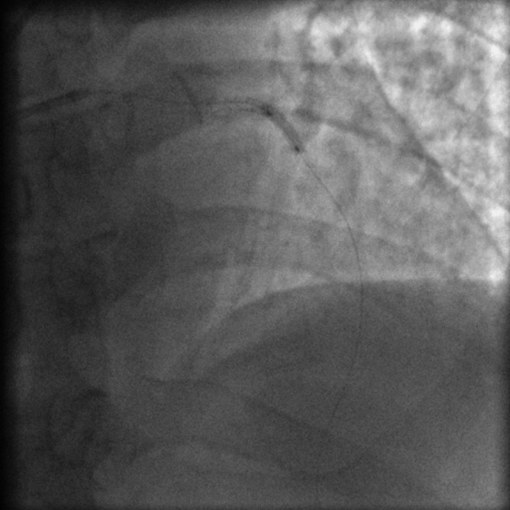

图1 首次PCI术中造影结果

分别于前降支远段和近中段(图1)置入2枚支架,均使用球囊后扩张,支架贴壁良好,膨胀充分,TIMI血流3级。术后使用阿司匹林300 mg qd +氯吡格雷75 mg qd。